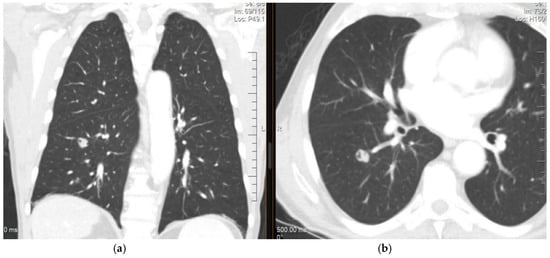

4. Diagnosis and Imaging of Lung Metastases

Imaging Studies